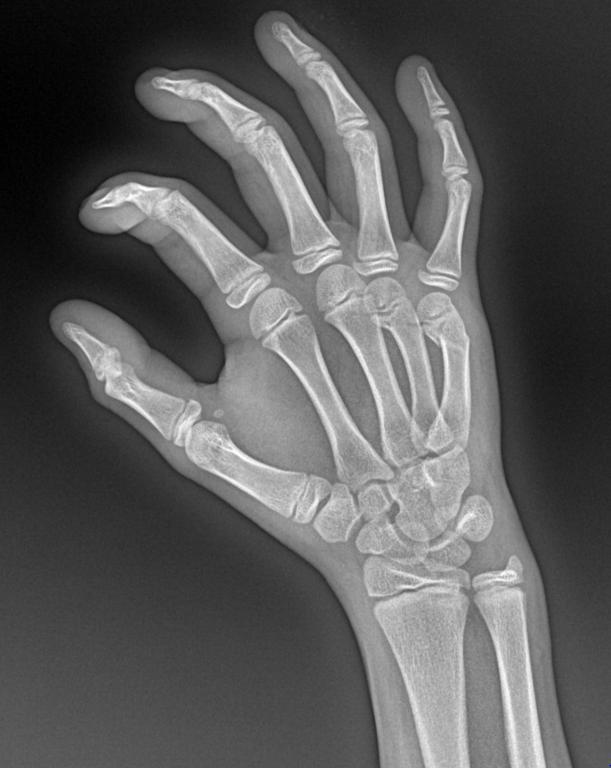

男 13y 外伤 右手正斜位